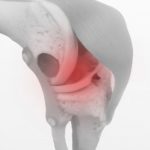

脊柱管狭窄症をストレッチで改善しよう!

2021年2月20日

足の痛みや痺れで自然と歩くのが嫌になり、お家にこもりがちになるとより脊柱管狭窄症が悪化します。 そこまで進行がはやいものではないので、自宅で簡単ストレッチを毎日行い、脊柱管狭窄症の症状を改善してみましょう。また、今は症状 […]

高齢者に多い脊柱管狭窄症って?

2021年2月18日

60~70代の10人に1人が発症している“脊柱管狭窄症”を前後半に分けてお話ししていきます。 当院でも脊柱管狭窄症の治療で来られる方がとても多くいらっしゃいます。そんな脊柱管狭窄症について皆さんはどれくらいご存じですか? […]